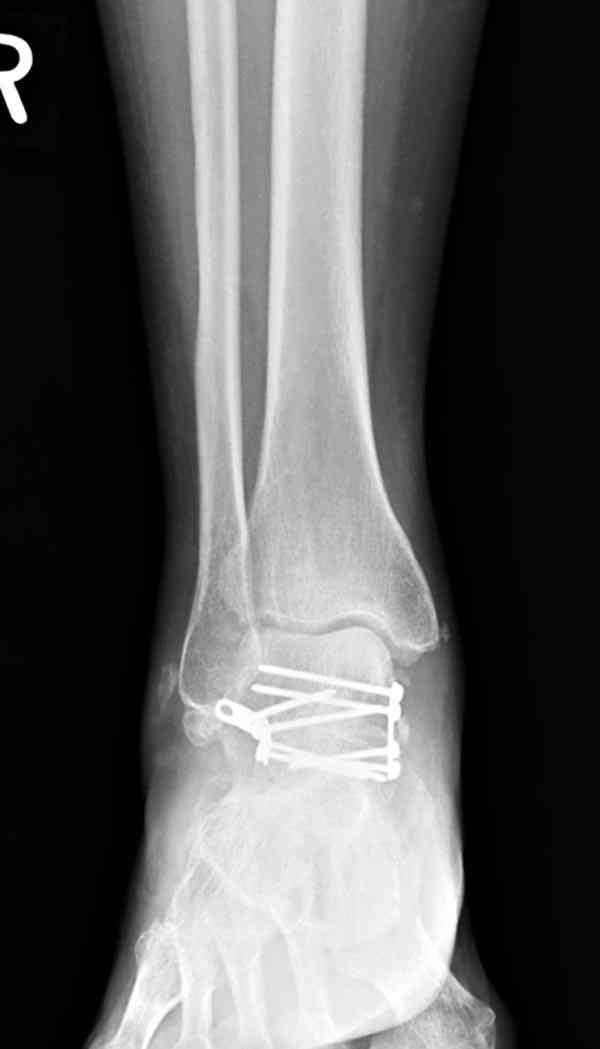

Случай с множественным оскольчатым переломом тарана оперированный из двойного доступа.

Через 14 мес.: